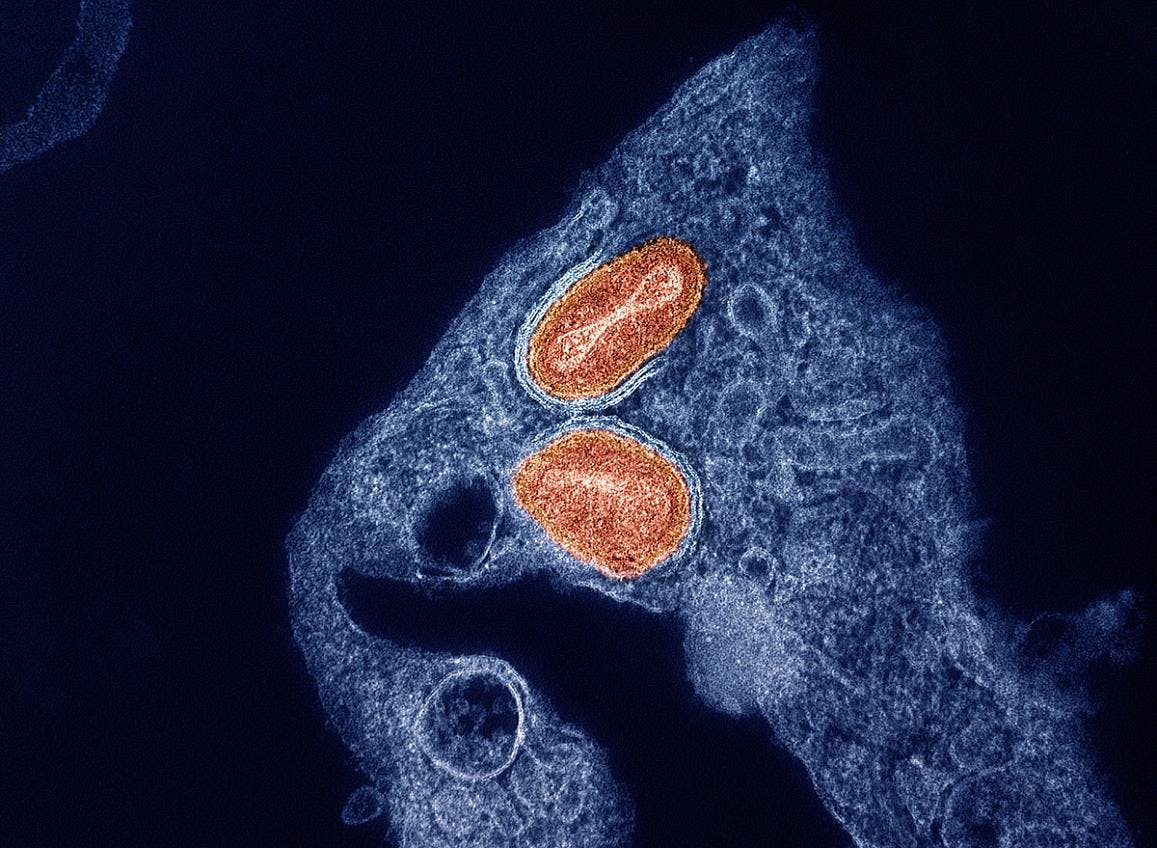

According to a Study of Tecovirimat for Mpox (STOMP) analysis, “tecovirimat did not reduce the time to lesion resolution or have an effect on pain among adults with mild to moderate clade II mpox and a low risk of developing severe disease.”